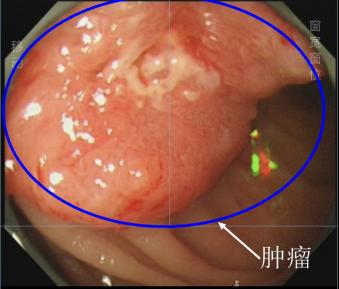

术前检查肠镜下,程先生(化名)的乙状结肠癌(蓝色圈部分)。